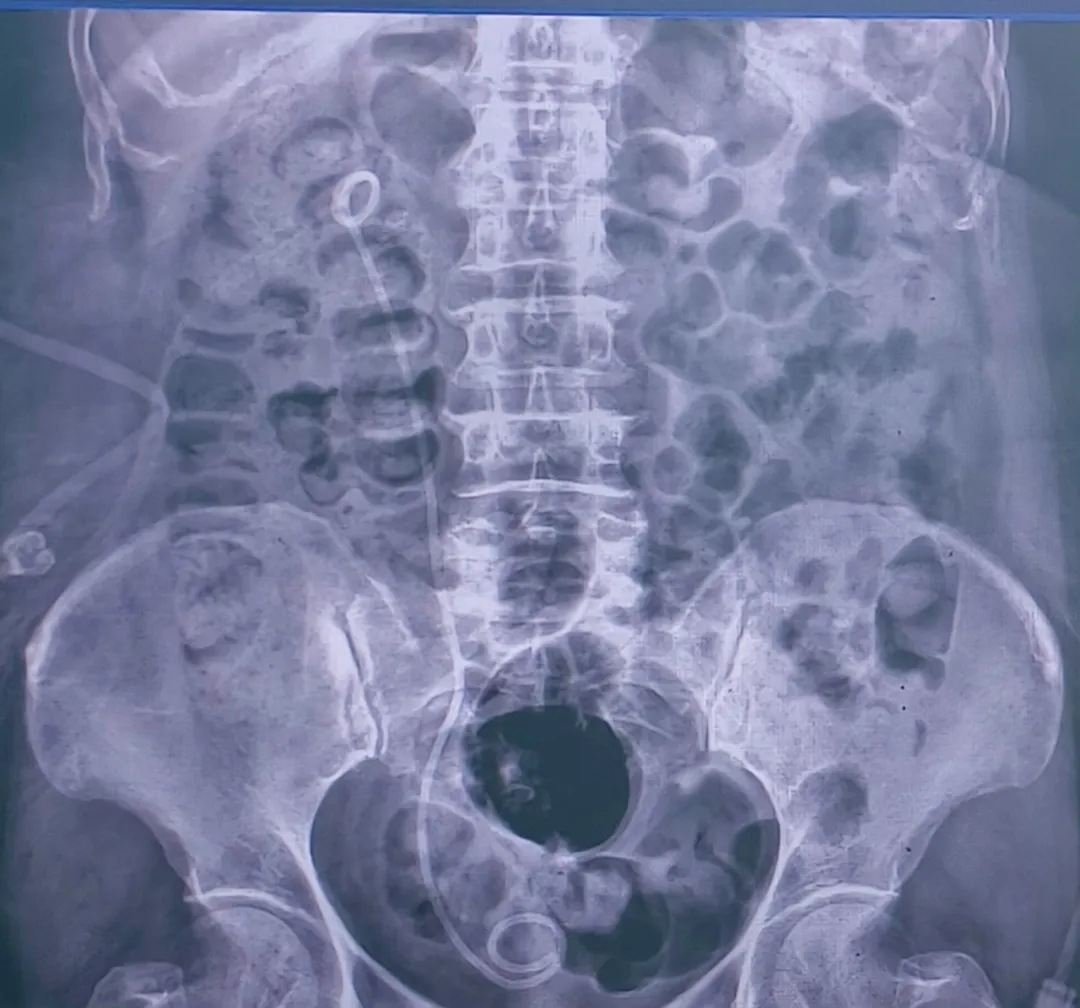

(术后腹部X光片示右肾巨大结石彻底清除)